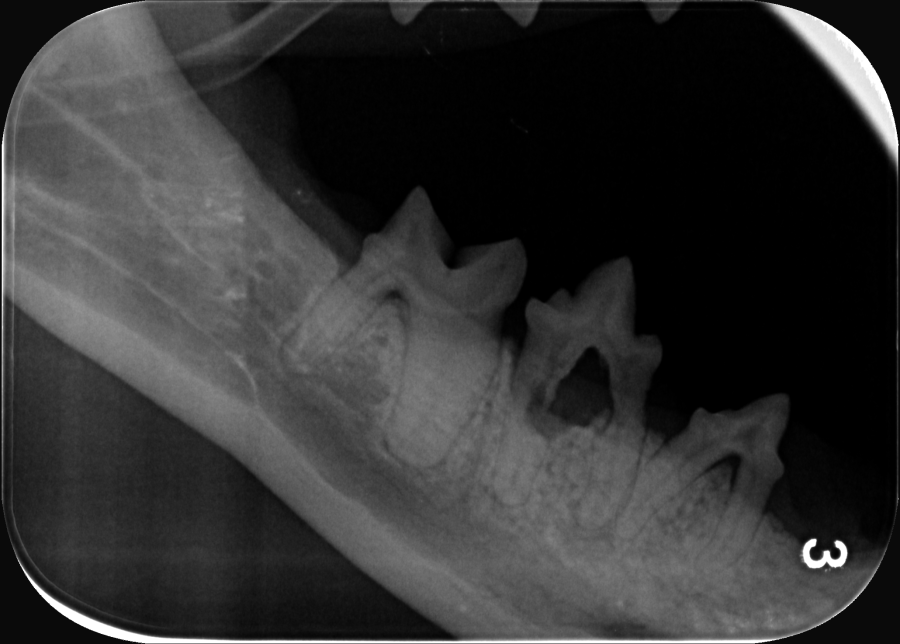

Zahnsanierungen bei Katzen werden grundsätzlich nur mit digitalem Röntgen aller Zähne und Zahnwurzeln durchgeführt, da vor allem Katzen sehr oft schmerzhafte Veränderungen der Zahnwurzeln haben, die nur im Röntgenbild zu sehen sind.